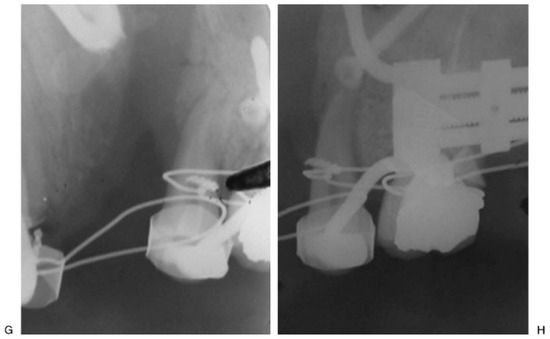

Figure 8. Initial aspect with alveolar defect (A–C). End trifocal alveolar bone transportation technique (ABT) (D,E). Radiographic image of end ABT with right transport disk (F), the common docking site (G), and the left transport disk (H). - Case 7 was a 30-year-old male patient with mandibular fracture sequel, treated with trifocal mandibular ABT (Figure 9).

Figure 9. Initial aspect (A); mandibular alveolar defect (B). Note the periodontal disease 28, 24, 23 (C); distractors in position (D); end trifocal alveolar bone transportation technique (E). Extractions of 24, 23, and 21; appropriate bone height at 220 weeks of follow-up (F,G).